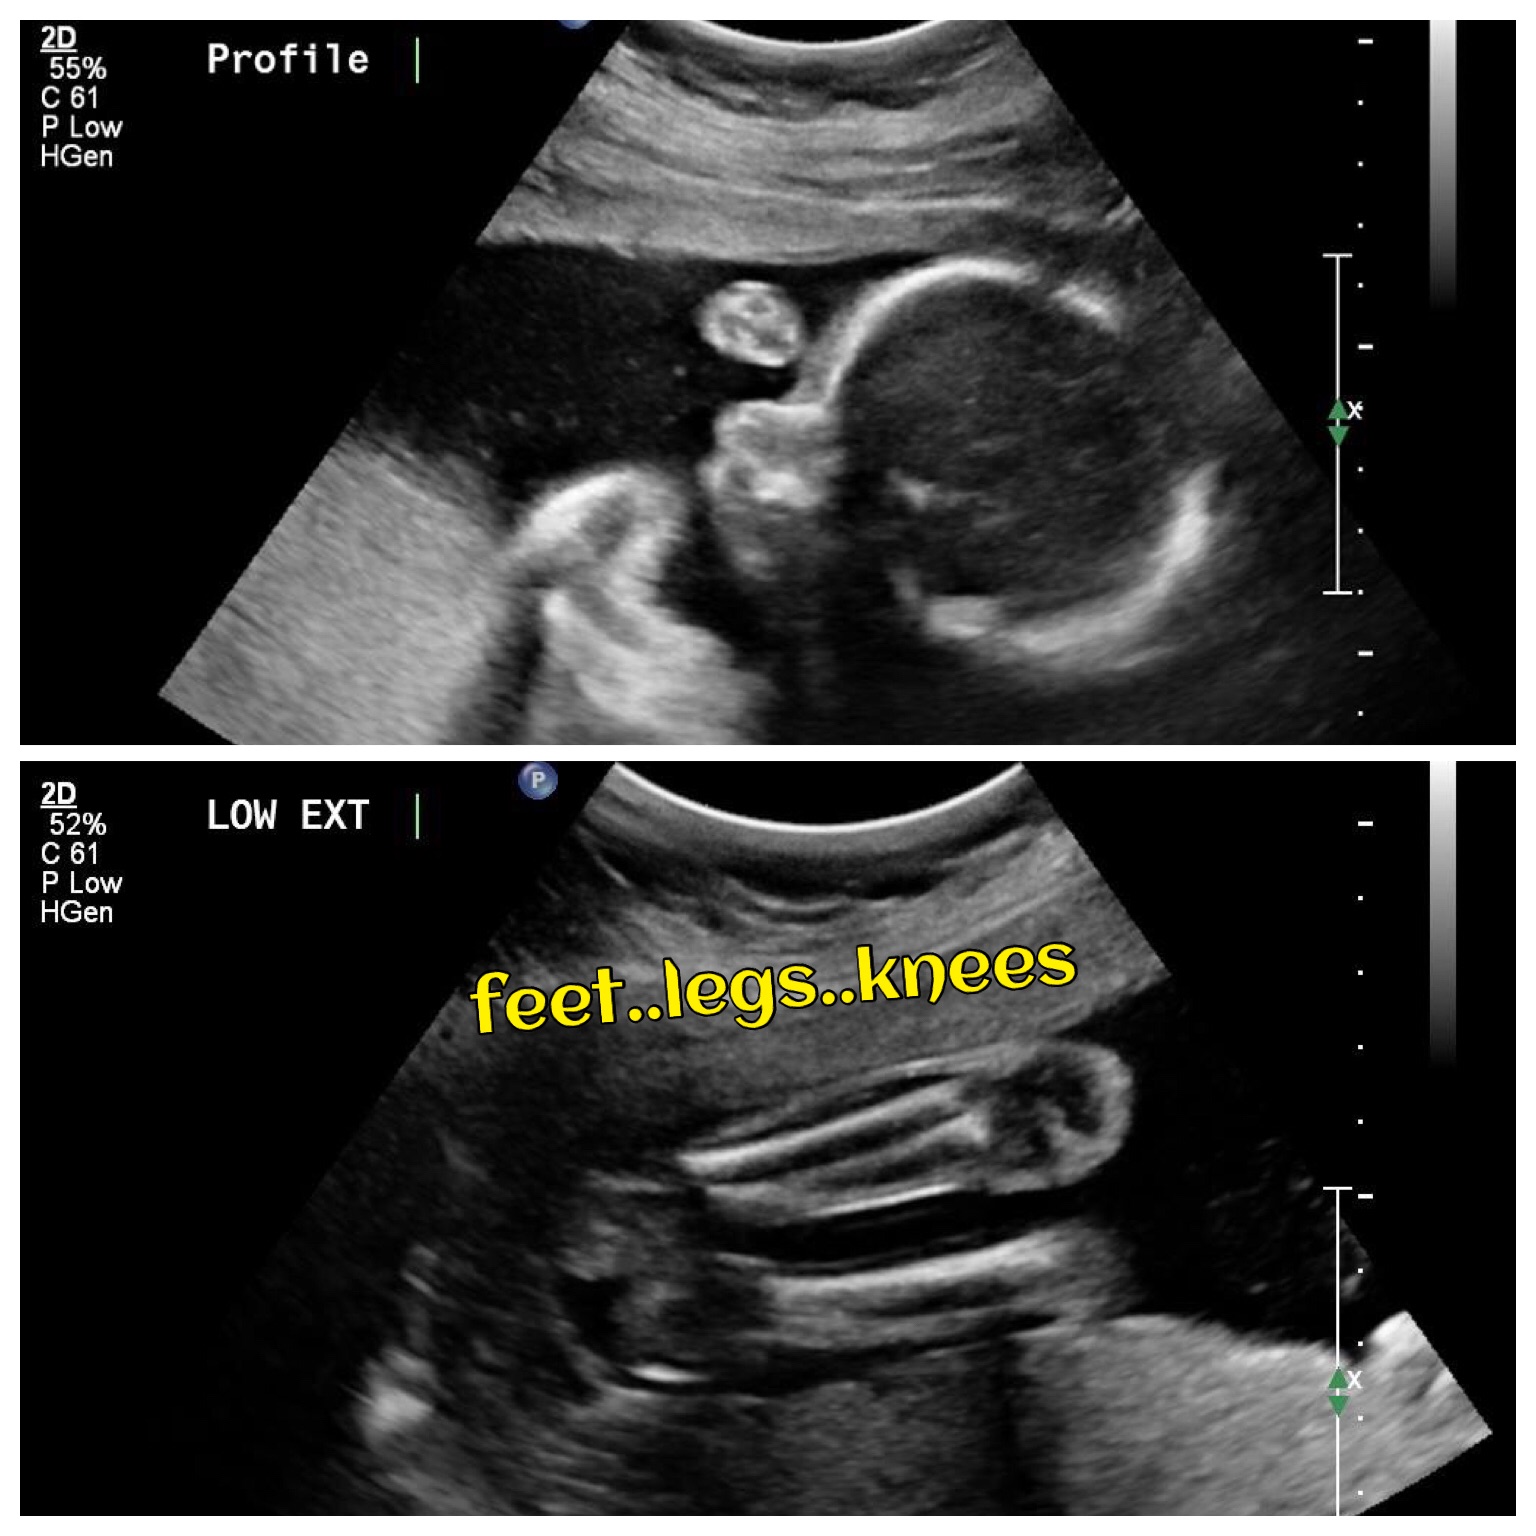

Well baby did not want to be in photos today lol Hand on the face the WHOLE time, kinda sucked but oh well. Back in 4 weeks. All measurements RIGHT on track which is weird for me. All my kids measured big!! 1 pound 9 ounces. Too smooshed for length. Only 2 good photos are a profile and some legs lol

Our little pumpkin was extremely active and the sonogram lady was seriously unamused at the wand kicking and back turning. This one is going to be TROUBLE